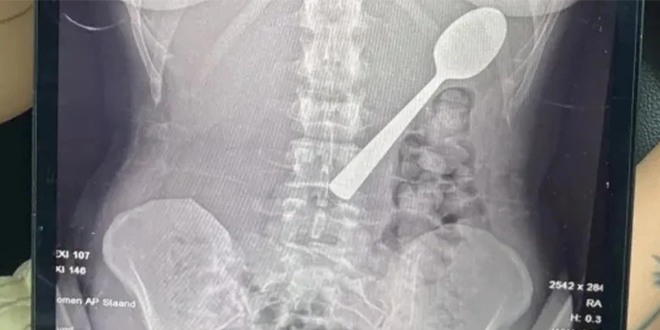

تعرضت امرأة بلجيكية لموقف صادم بعدما ابتلعت ملعقة بطول 17 سنتيمتراً عن طريق الخطأ أثناء تناولها الطعام، وذلك بعد أن قفز كلبها على جسدها بشكل مفاجئ.

وقالت ريمي أملينكس، البالغة من العمر 28 عاماً، إنها اضطرت للاختيار بين الاختناق أو ابتلاع الملعقة، مشيرة إلى شعورها بأنها “انزلقت بسلاسة إلى معدتها”.

وأضافت في تصريحات صحفية أنها كانت تجلس على الأريكة أثناء تناول الزبادي، وعندما قفز كلبها من نوع “هنغاريان فيزلا” المعروف بنشاطه، تفاجأت بشكل كبير ما أدى إلى انحشار الملعقة في حلقها بالخطأ، فحاولت إزالتها بيدها، لكن الموقف كان سريعاً جداً ولم يكن أمامها سوى ابتلاعها لتجنب الاختناق.

وبعد تناول العشاء، أدركت خطورة الموقف، وذهبت إلى الأطباء الذين أبلغوها أن الملعقة كبيرة جداً لتخرج طبيعياً، ما استدعى انتظار إجراء منظار معدة.

وأُزيلت الملعقة بعد يومين تحت التخدير الموضعي، حيث اضطر الأطباء لتدويرها داخل المعدة، ما تسبب في نزيف بسيط، وأكدت ريمي أن الحادث لم يترك أي أضرار دائمة، لكنها تعرضت لالتهاب في الحلق ونزيف في المعدة طفيف وحساسية لبعض الوقت.